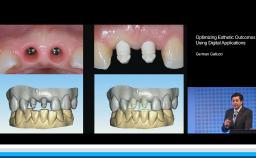

German Gallucci